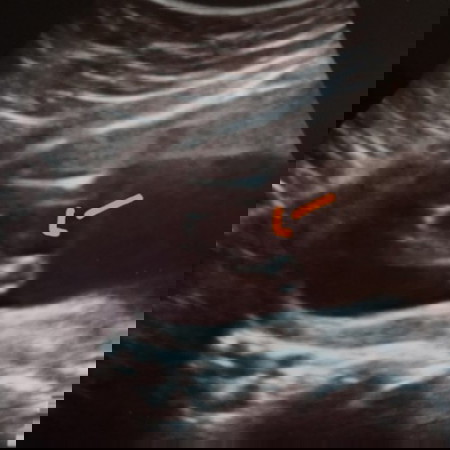

ลูกสาว😍😍 เดานะคะ. แรกๆไม่รู้ว่าท้องซาวน์เหมือนมีจู๋ จริงๆแล้วคือสายรก เจาะน้ำคร่ำ ผลชัวร์เลยค่ะได้ลูกสาวเหมือนกัน😍😍

หญิงแน่นอนค่ะ กลีบมาเลยค่ะ

น่าจะผู้หญิงนะคะ

น่าจะผู้หญิงค่ะ